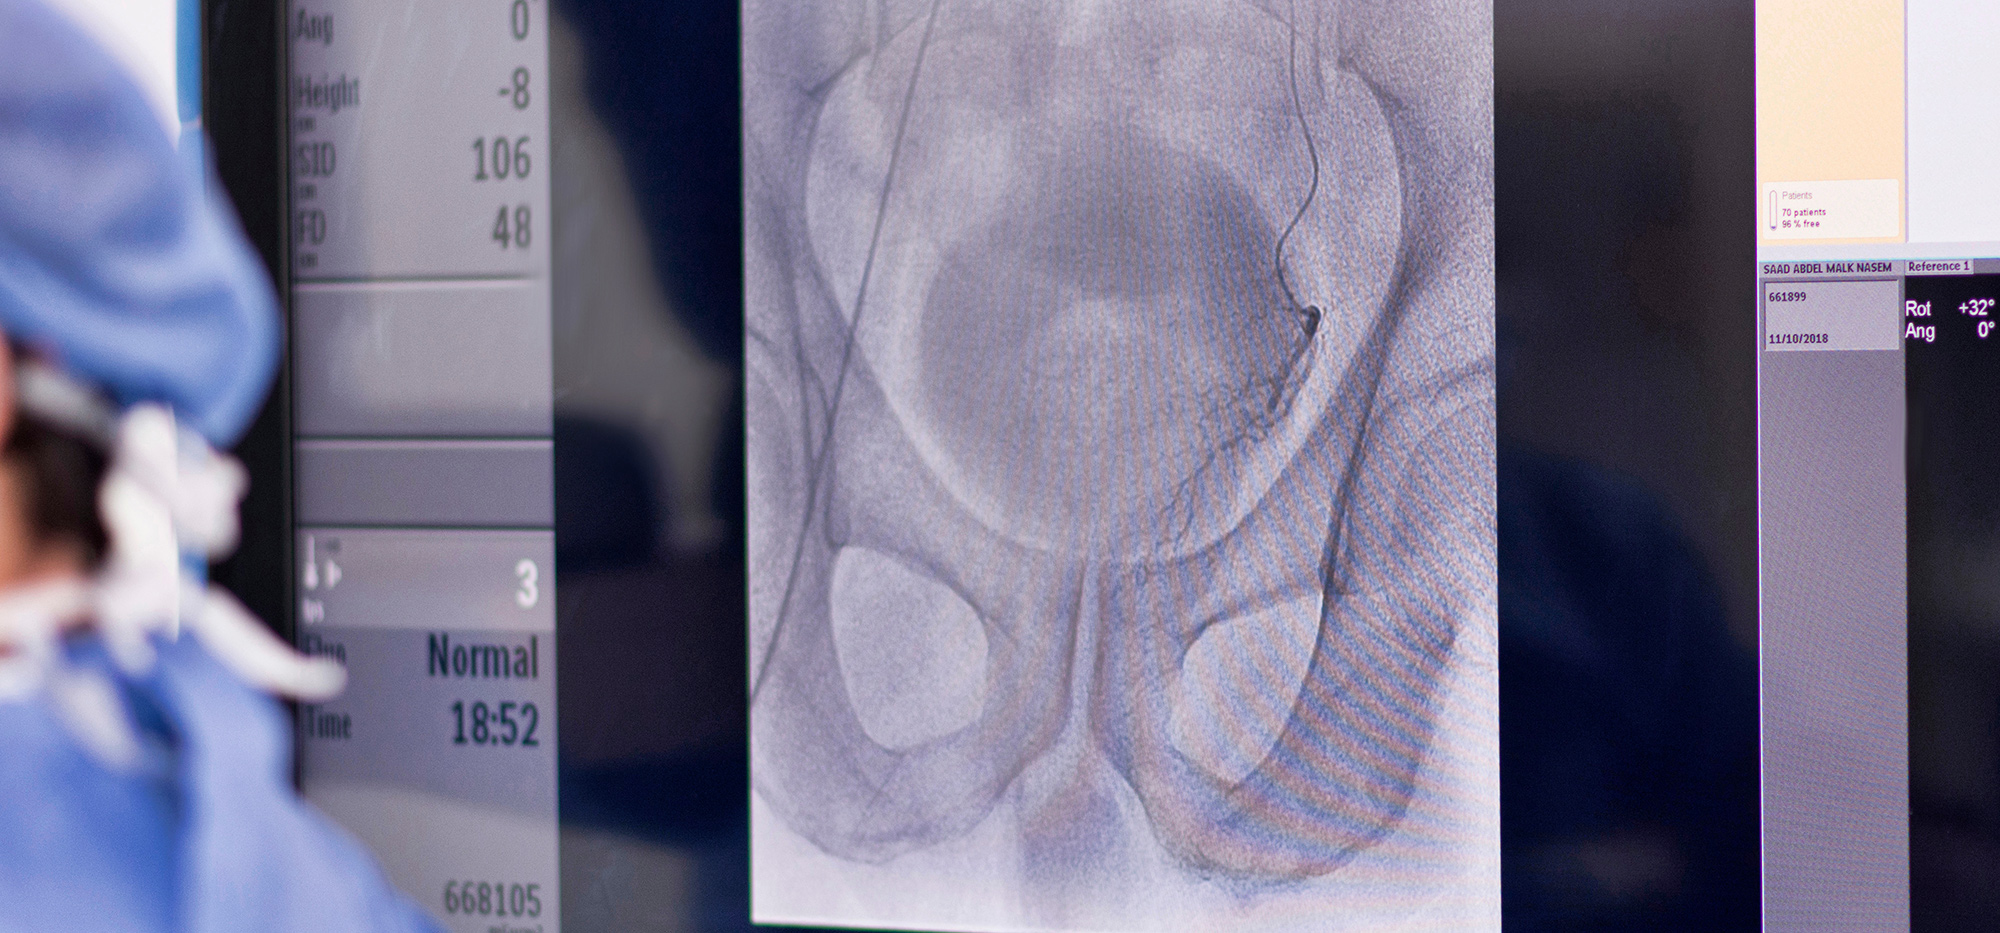

Prostate Artery Embolisation (PAE) is a minimally invasive procedure performed by interventional radiologists to treat benign prostatic hyperplasia (BPH).

The procedure is carried out under X-ray guidance, allowing the radiologist to navigate a microcatheter (a very fine tube) to the prostate arteries that supply blood to the enlarged prostate. Once the catheter is in position, tiny plastic beads are injected into these arteries, blocking the blood flow to the prostate.

The procedure begins with a catheter being inserted into an artery in the groin or wrist. Using X-ray guidance, the interventional radiologist advances the catheter towards the prostate arteries.

Once the catheter reaches the prostate arteries, tiny beads are then injected into these arteries to block the blood flow to the prostate. By cutting off the blood supply, the prostate tissue gradually shrinks, reducing pressure on the urinary tract and alleviating symptoms.